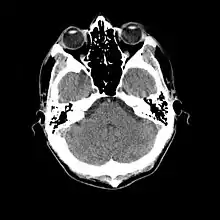

Coupe de scanner cérébral, normal au cours d'une méningite.

L'examen complémentaire essentiel à l'identification d'une méningite est l'analyse du liquide cérébrospinal obtenu par ponction lombaire[27]. Toutefois une telle ponction est contre-indiquée en cas de masse cérébrale (tumeur, abcès) ou d'hypertension intracrânienne, pouvant entraîner un engagement cérébral. En cas de situation à risque (traumatisme crânien, déficit immunitaire, signe neurologique focal, signe clinique d'hypertension intracrânienne), une imagerie cérébrale préalable est recommandée, avec un scanner ou une IRM[10],[26],[28]. C'est une situation concernant potentiellement environ 45 % des cas adultes[9]. Lorsqu'une imagerie est effectuée avant la ponction ou que celle-ci se montre difficile à réaliser, il est suggéré d'administrer un traitement antibiotique immédiatement afin de ne pas retarder le délai de mise en route du traitement[10], surtout si une telle attente est prévue pour dépasser 30 minutes[26],[28]. Souvent, lorsque l'imagerie n'est pas faite initialement, elle est faite plus tard dans les cas où il existe une complication[3].